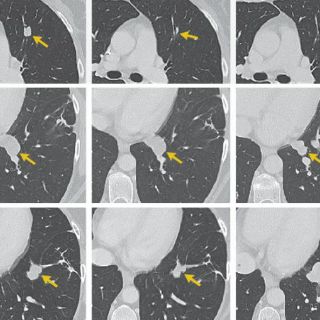

LOS ÁNGELES, ESTADOS UNIDOS (28/FEB/2017).- Una terapia genética experimental que convierte las células sanguíneas del paciente en agresoras contra el cáncer resultó eficaz en un importante estudio en el que más de un tercio de enfermos avanzados de linfoma no mostraron señales de la enfermedad seis meses después del tratamiento, dijo su fabricante el martes.

En el 82% de los pacientes, el cáncer se redujo al menos a la mitad en algún momento del estudio.

Los enfermos padecían uno de tres tipos de linfoma no Hodgkin, un cáncer de sangre, y todos los demás tratamientos habían fracasado. El tiempo medio de supervivencia de esos enfermos es de seis meses.